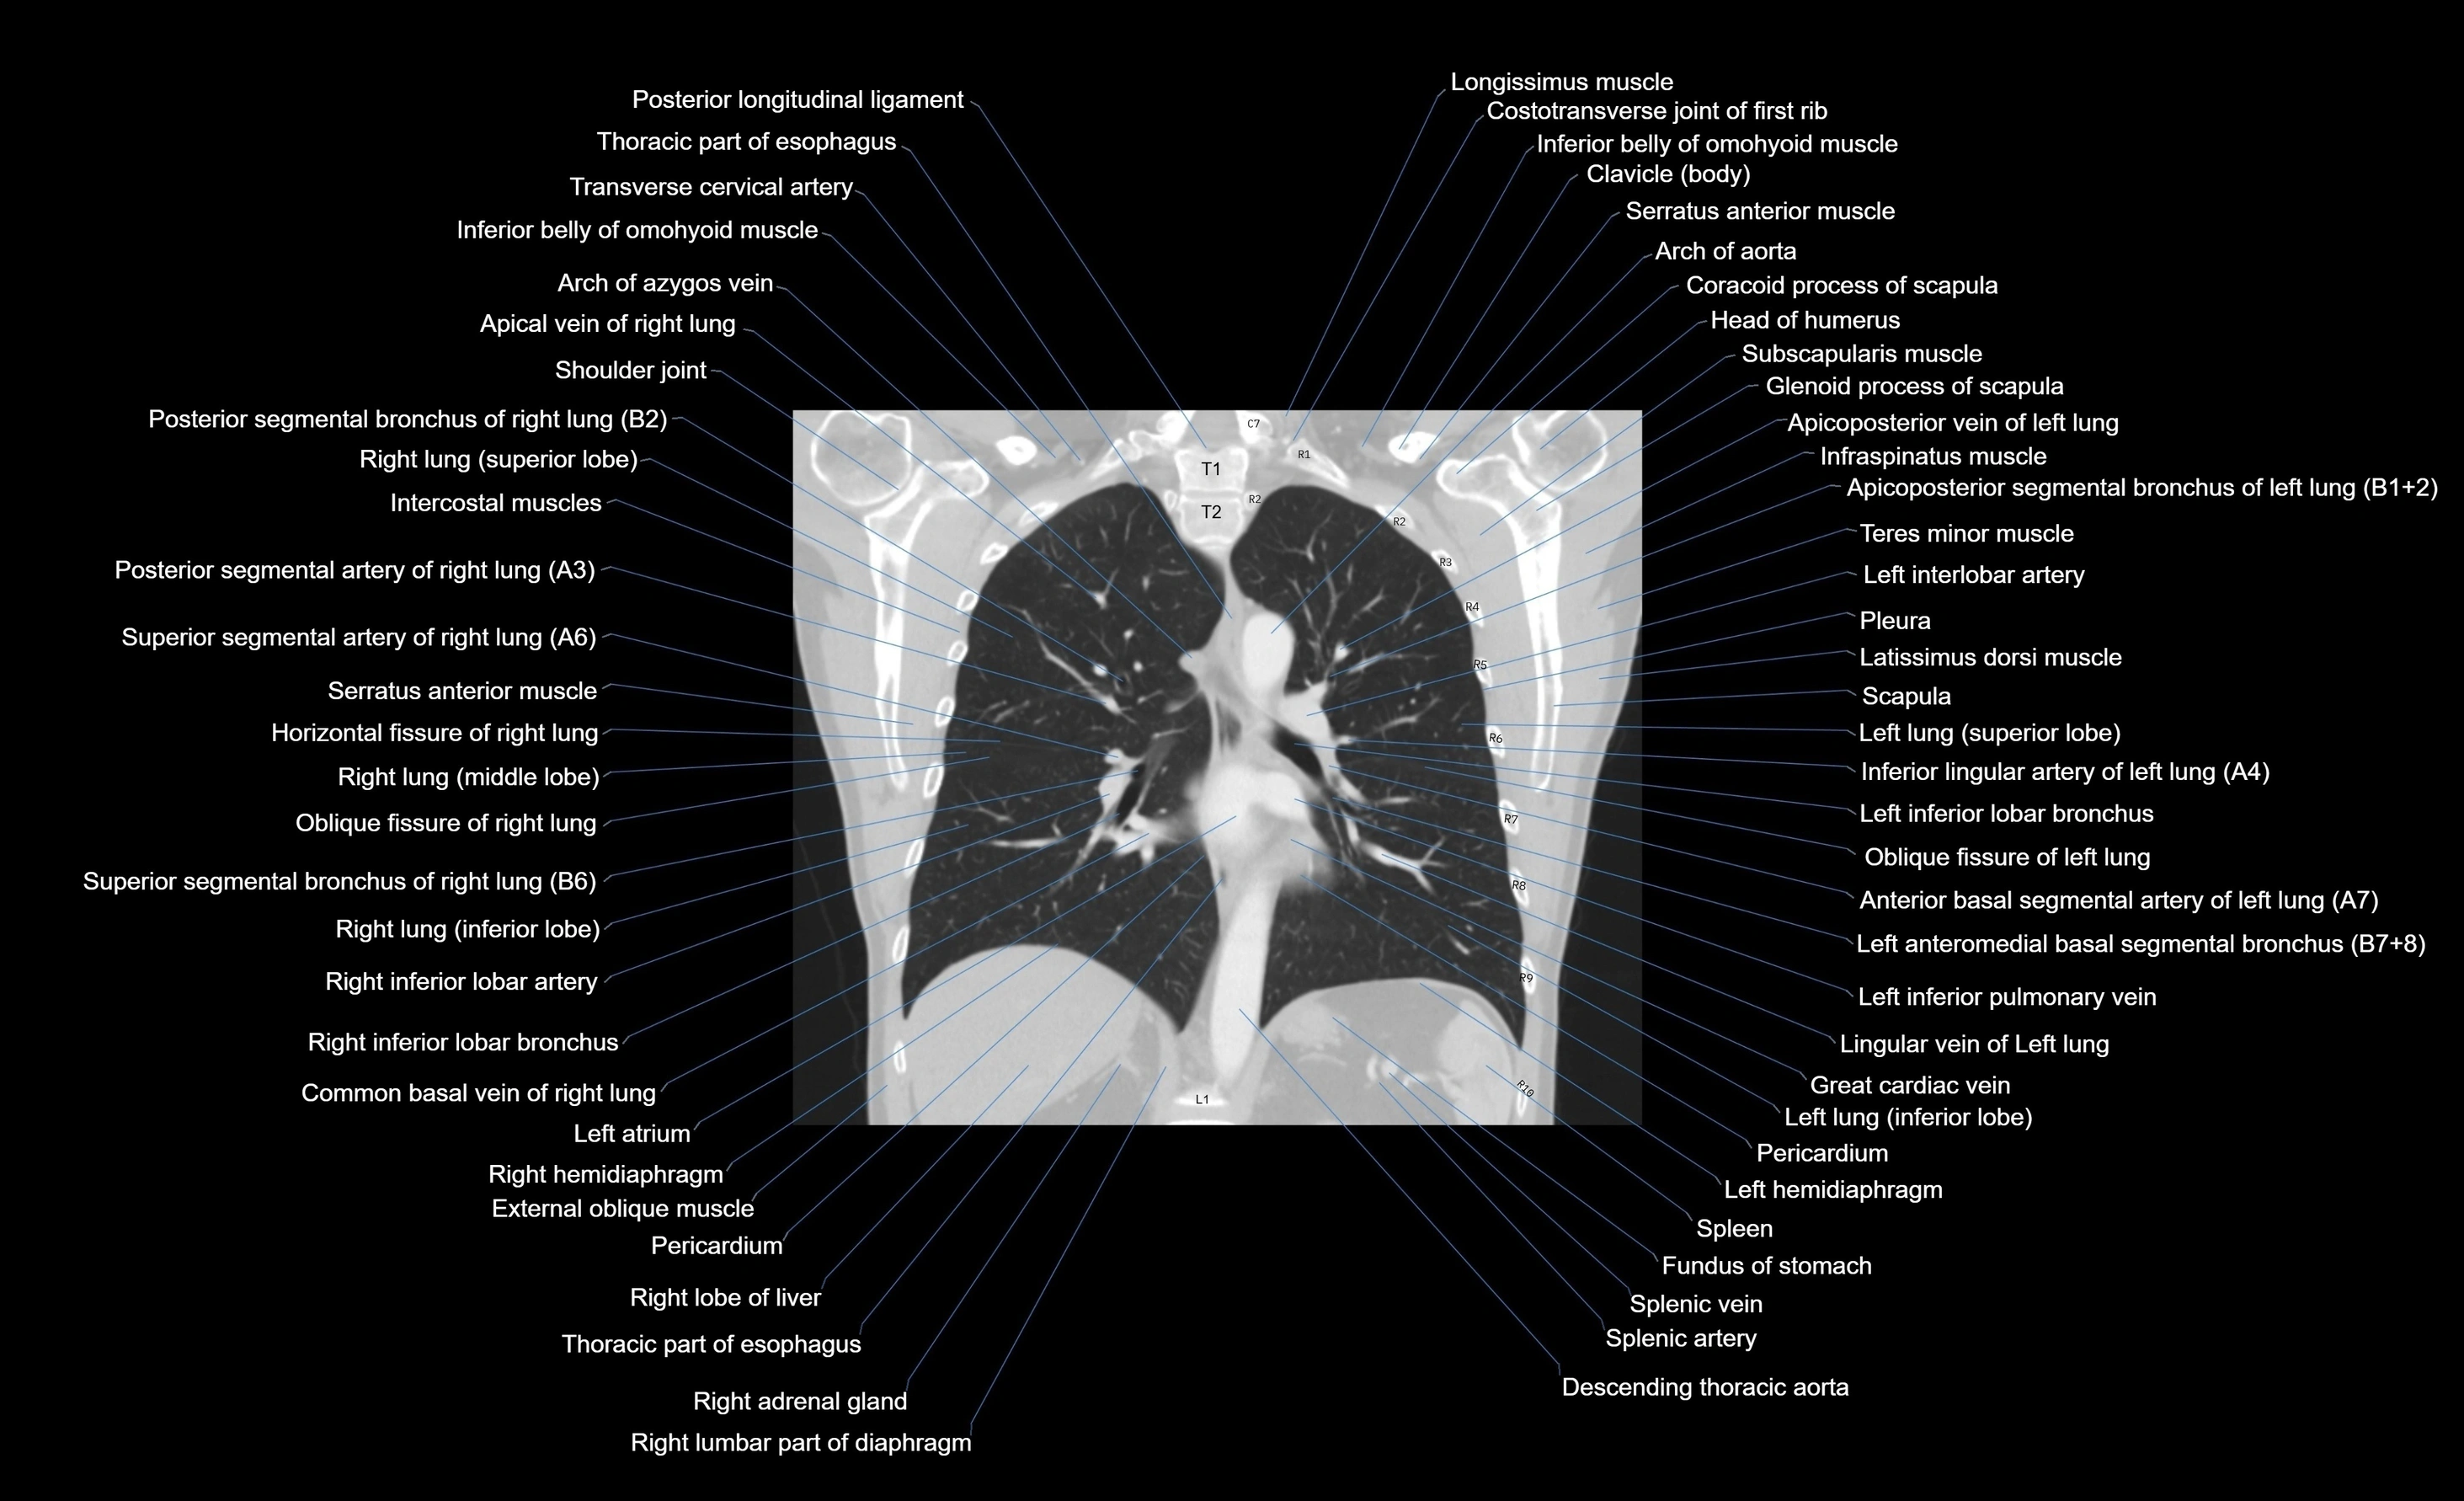

CT images